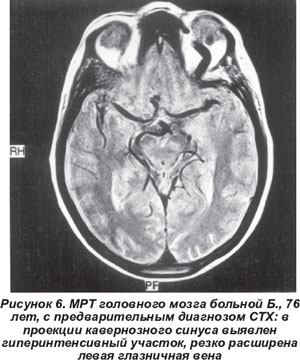

Тромбоз кавернозного синуса диагностирован у женщины 76 лет с подострым развитием тотальной офтальмоплегии слева, выраженным хемозом и экзофтальмом. При МРТ в проекции кавернозного синуса выявлен гиперинтенсивный участок и резко расширенная левая глазничная вена (рис. 6).